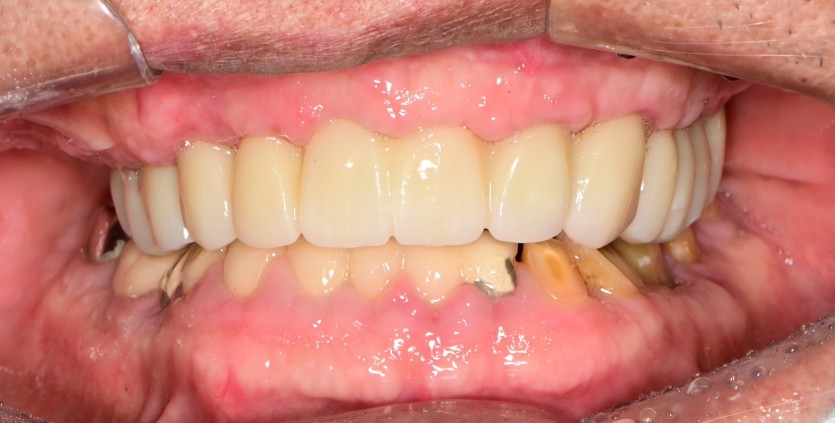

상악 전체 임플란트 증례입니다.

10개의 임플란트로 완성하였습니다.